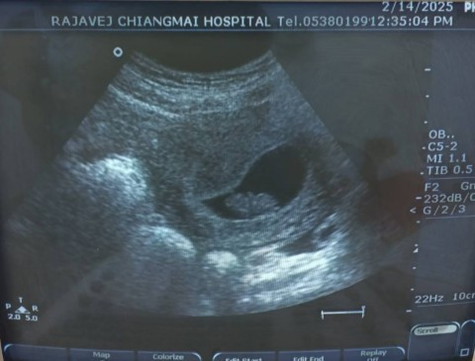

8 สัปดาห์ 4 วัน

คุณหมอบอกน้องมี แขน ขา หัวใจเต้นตุบๆๆๆ แล้วค่ะ

แม่ท้อง